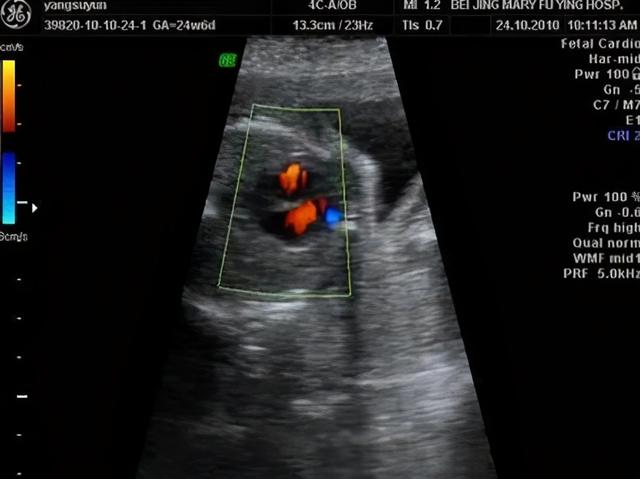

在检查中胎儿心脏部位有强光点基本上时没有什么问题的,超声印象显示的是超声表现,并不是说胎儿一定患有心脏问题,只要孕妈之前做了唐筛基本上是不会出现预料之外的事情,孕妈实在担心的话也可以进行无创DNA的检查,只要该检查是没有问题的,那么胎儿心脏处出现的“强光点”绝对不会有任何的问题,因为四维是对宝宝整体的一个大排畸,所以孕妈们一定要在准确的时间点去进行检查,如果超过四维的检查时间是没有办法在进行大排畸的。

“心脏强光点”是四维检查经常出现的一种现象,该强光点虽然有可能是“病理性”的。但是绝大部分的胎儿并不会受其影响,随着时间的变化,这些强光点也会慢慢的消失不见,孕妈需要冷静的去对待。

以积极的心态面对胎儿的各种问题固然是正确的,但是心脏强光点也有一定概率是宝宝心脏发育畸形,导致宝宝出现心脏异常常见的问题是由于染色体导致的,这种概率虽然有,但是概率非常低,其几率为百分之一,所以孕妈遇到B超检查发现胎儿心脏有强光点可暂时不处理,观察一段时间以待确诊,观察期通常为30天左右,若强光点在四周后进行检查依旧存在,产科主治医生会让孕妈做一些检查,如心脏彩超和无创DNA来进行确诊。

强光的表现也表示胎儿有可能有NT增宽、肾盂分离、肠道强回声、四肢长骨短、鼻骨短小等临床表现。如果宝宝强回声光点只出现在左心室,而且只有一枚,那么孕妈可以放心。这是没有什么临床意义,但是如果右心室也有的话,那么就需要进行下一步检查。

通常强光点随孕周增加而缩小,到37周的时候就已经完全消失,但是也有一部分一直存在,如果说单纯光点5mm,这种情况是因为钙化现象,99%是没事的。